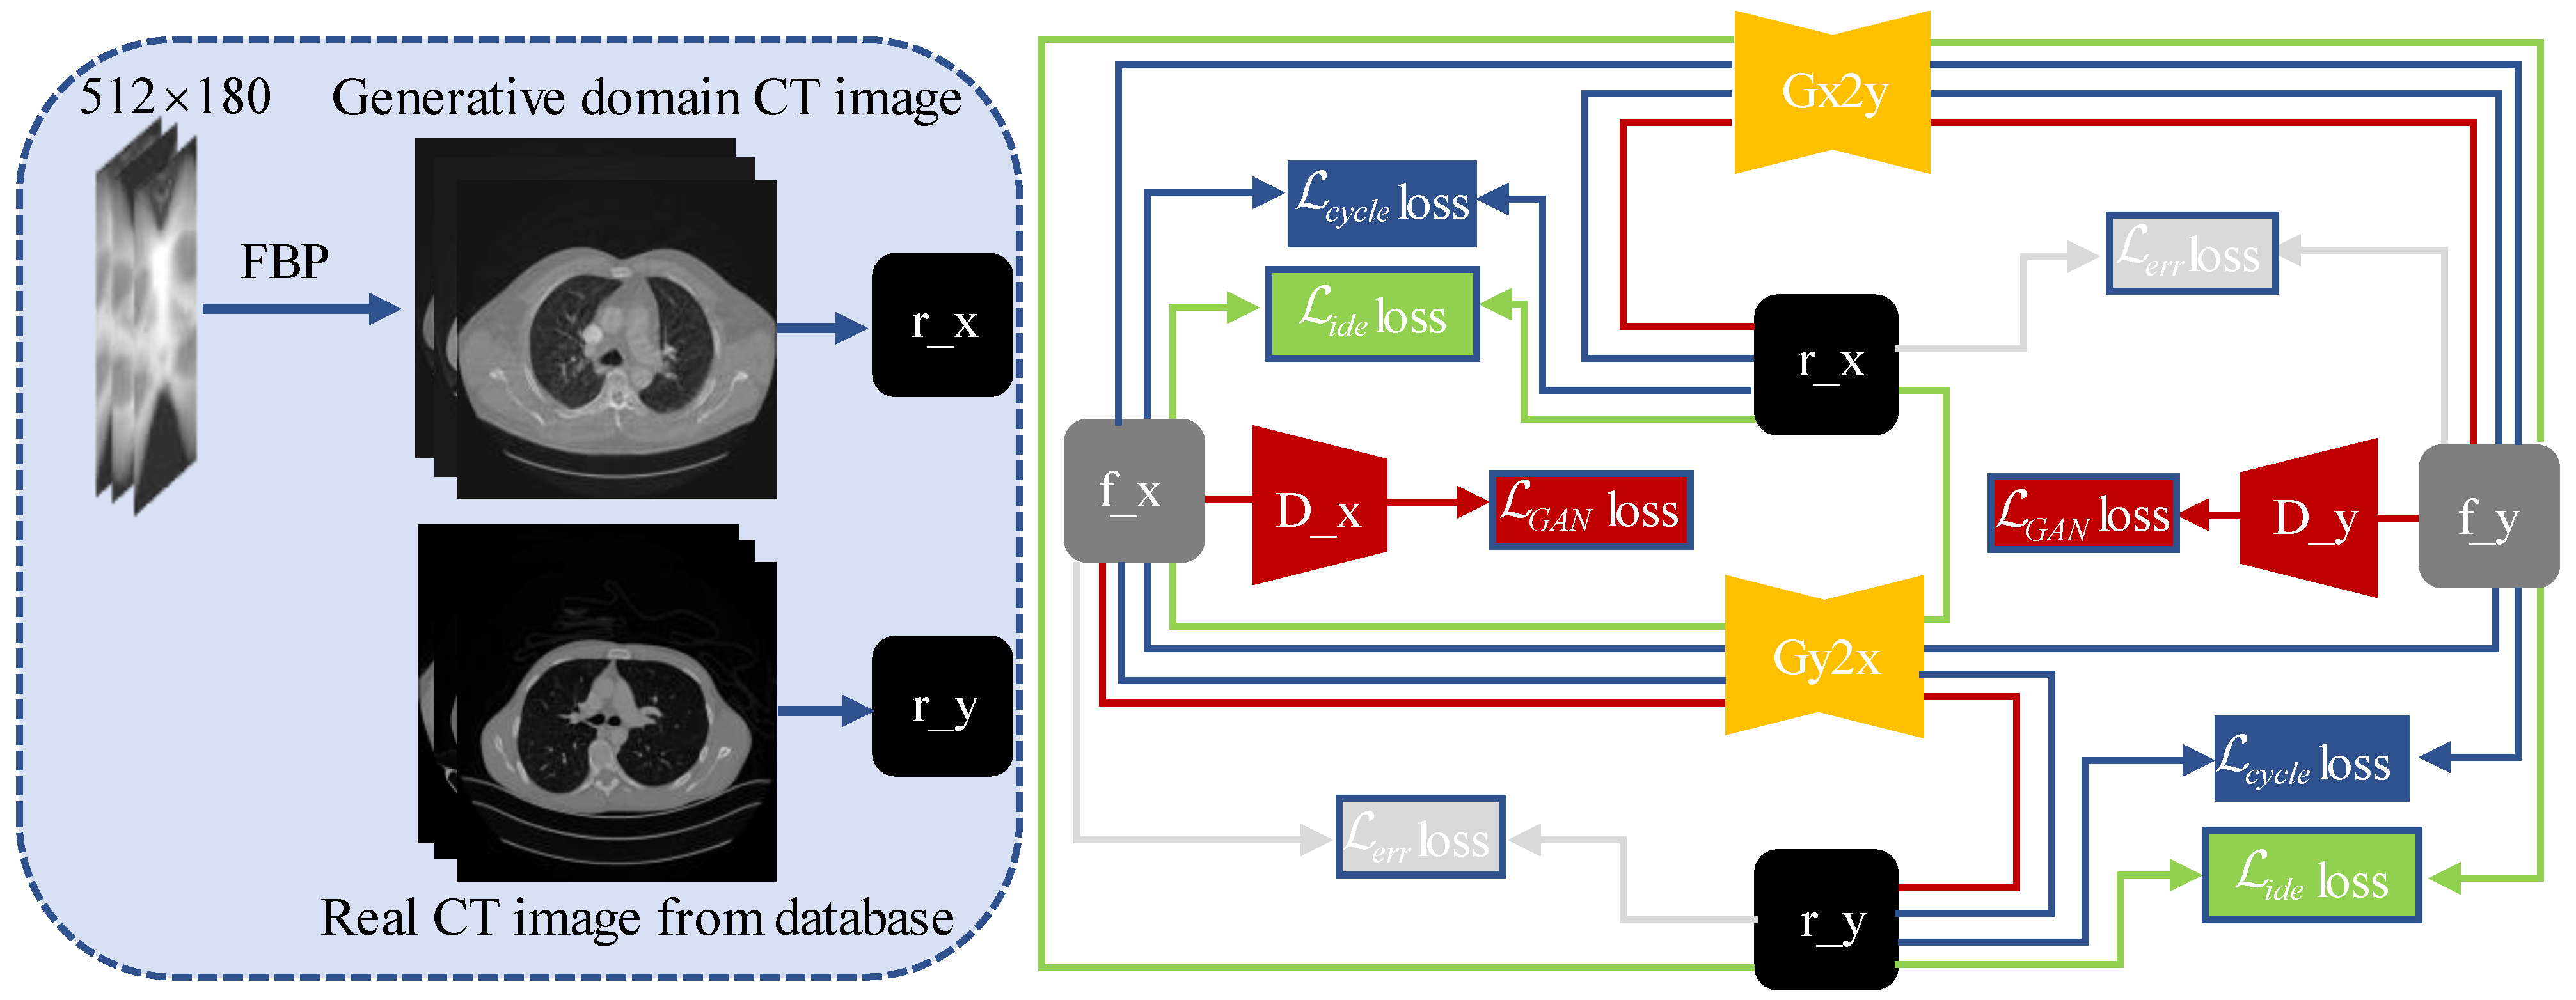

2.2. Artifact Removal Generative Adversarial Network (AR-GAN)